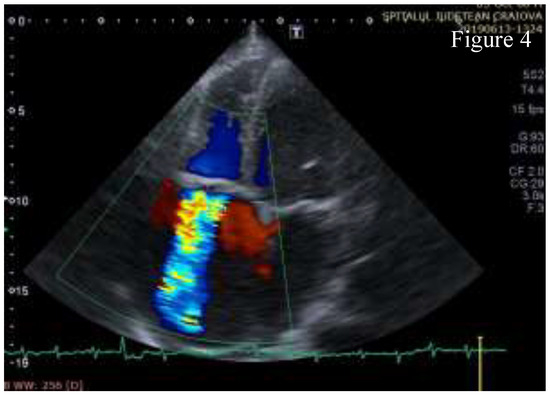

Figure 4.

A4C Color Doppler - severe tricuspid regurgitation.